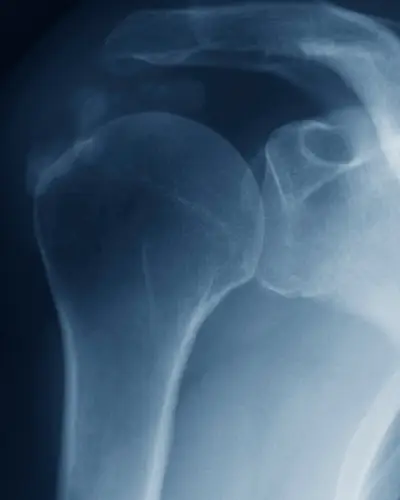

The rotator cuff muscles cross the shoulder joint to act as a compressive cuff to maintain the stability of the shoulder joint when it is moving. The shoulder joint has the greatest amount of movement of any joint in the body and is therefore also the most unstable, hence the frequency of rotator cuff tear injuries. Like any joint, the shoulder has ligaments to provide stability, but it relies heavily on the rotator cuff for dynamic stability.

Think of the shoulder joint like a golf ball sitting on a tee. The golf ball is much larger than the tee. To help with the stability of the joint there is the labrum (blue). It makes the surface of the tee a little larger.

The main stability though, comes from the muscles. They act like ropes to hold the ball on the tee as the ball rolls around. The rotator cuff muscles blend together almost forming a blanket which covers the entire ball of the joint.